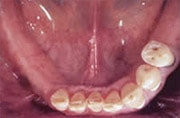

Gestern

herausnehmbare Teilprothese mit Klammern